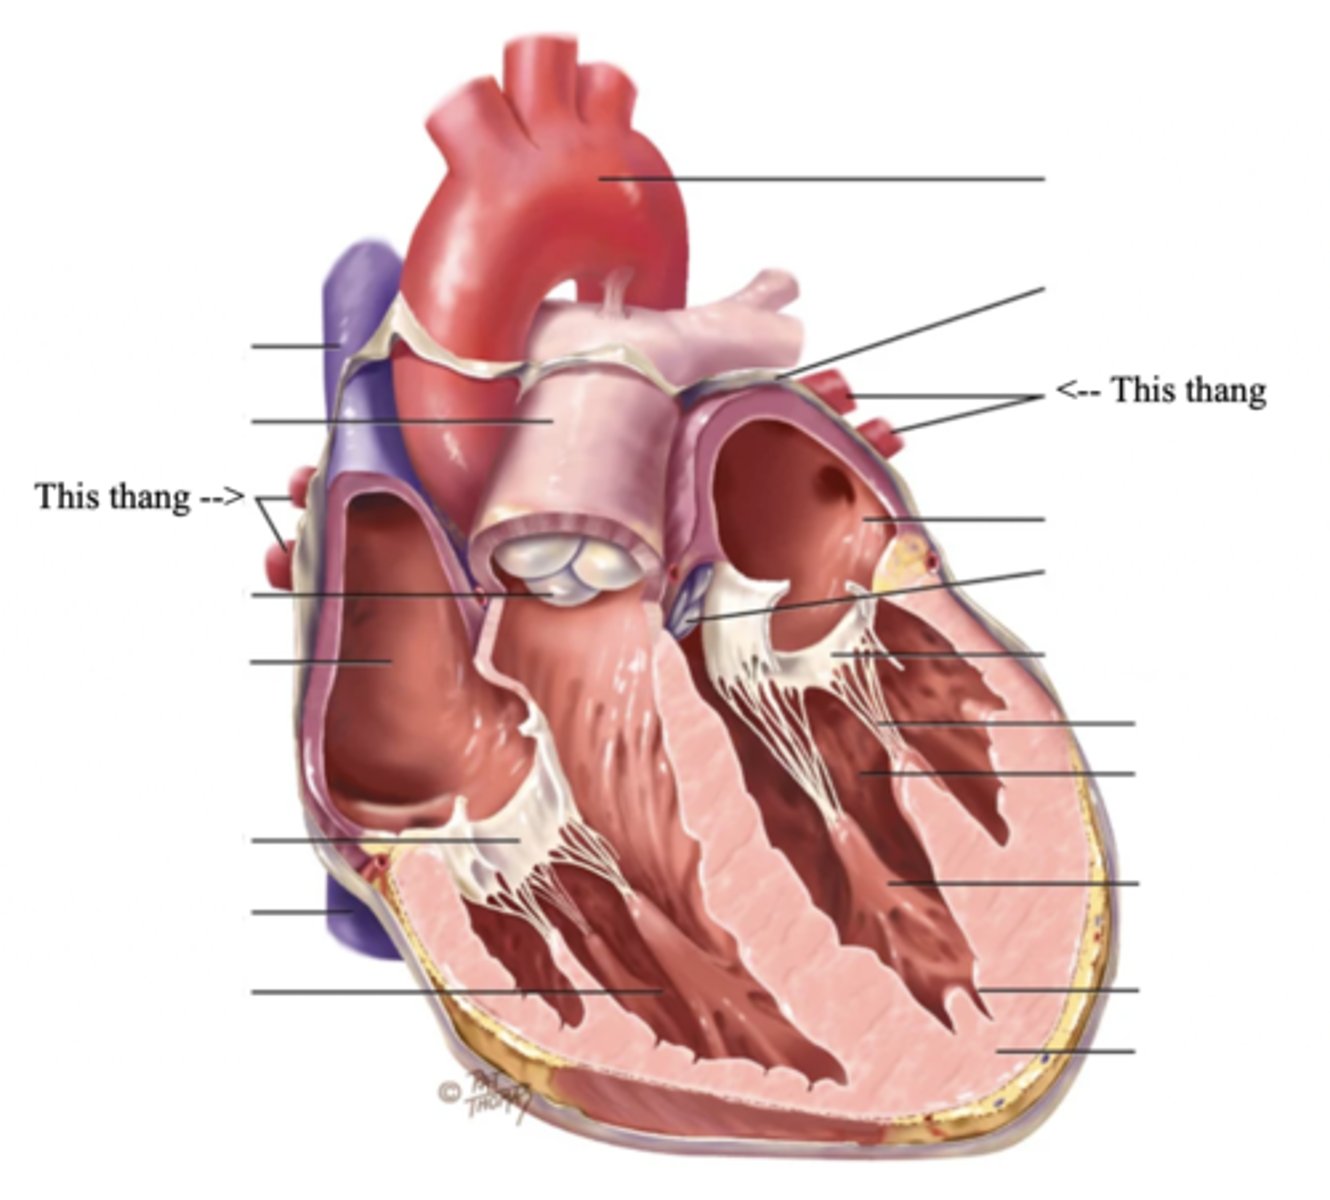

Anatomy of the Heart

2 Types of Chambers in the Heart

- Atrium

- Ventricles

Atrium (2)

A thin-walled reservoir for holding blood, located at the upper chamber of the heart

Ventricle (2)

The thick walled muscular pumping chamber of the heart located at the bottom chamber of the heart

2 Main Types of Valves of the Heart

- Atrioventicular

- Semilunar

Atrioventricular Valves (AV) (2)

The valves that separate the atria and the ventricles

The 2 Atrioventicular Valves of the Heart

- Tricuspid

- Mitral

Tricuspid Valve

- The right AV valve separating the right atrium from the right ventricle

- Connected by 3 chordae tendinae

Mitral (Bicuspid) Valve

- The left AV valve separating the left atrium from the left ventricle

- Connected by 2 chordae tendinae

Chordae Tendinae

Fibers (heart strings) attatched to the tricuspid and mitral valve which pull it closed when papillary muscles contract, preventing back flow of blood

Semilunar Valves (SV) (2)

Valves located between the ventricles and the pulmonary arteries and aorta

The 2 Semilunar Valves of the Heart

- Pulmonic

- Aortic

Pulmonic Valve

The SV valve of the right side of the heart

Aortic Valve

The SV valve of the left side of the heart

The 4 Great Vessels of the Heart

- Superior/inferior venae cavae

- Pulmonary artery

- Pulmonary veins

- Aorta

Superior/Inferior Venae Cavae

The large veins that empty into the right atrium of the heart and return unoxygenated venous blood to the right side of the heart

Pulmonary Artery

Artery carrying oxygen-poor blood from the heart to the lungs

Pulmonary Veins

Veins carrying oxygenated blood from the lungs to the heart

Aorta

The largest artery in the body which carries oxygenated blood from the heart throughout the body